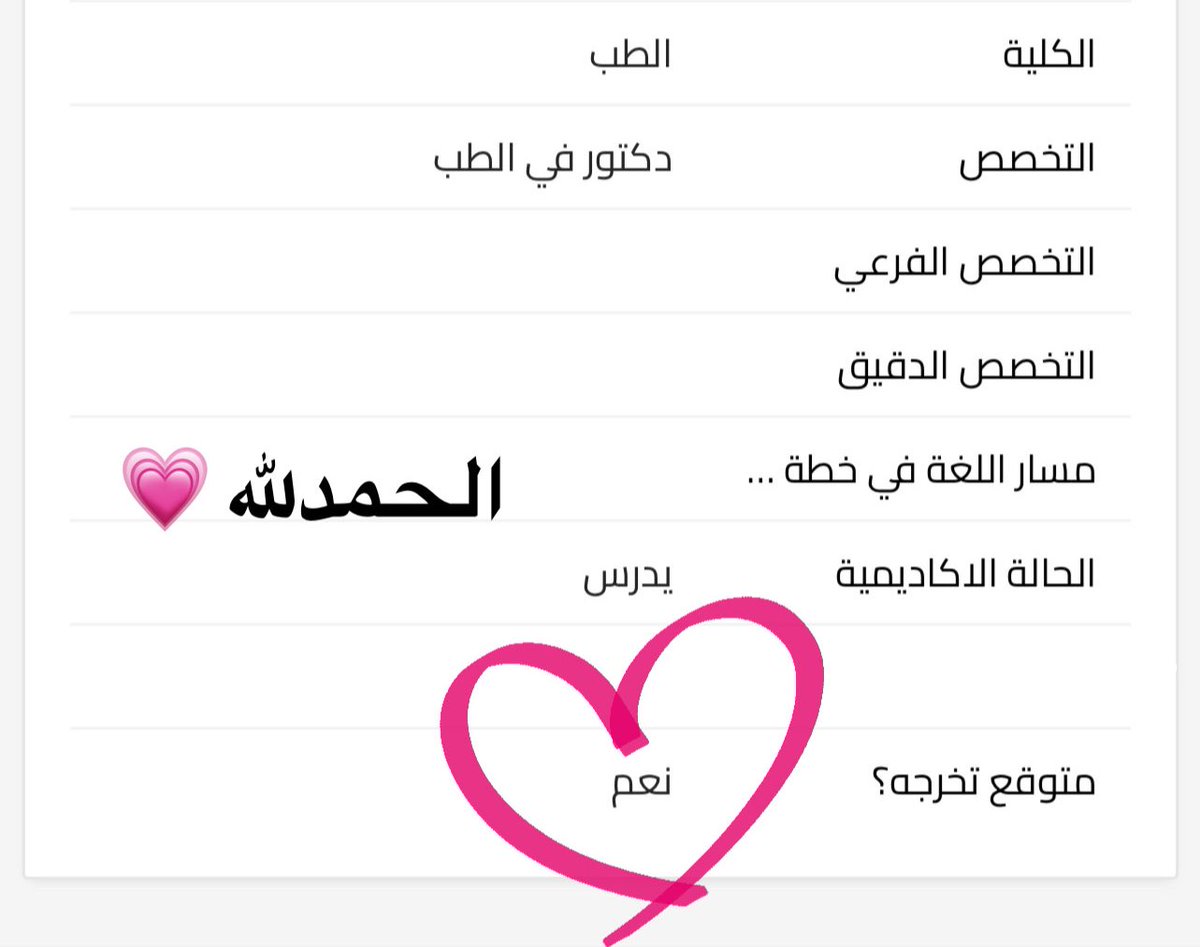

درس ال Jaundice انا ذاكرته 100 مرة مثلا ذاكرته في الاطفال والباطنة والجراحة وكل مرة براجع عليه بيبقا كل معلوماتي ان العيان بيبقا لونه اصفر